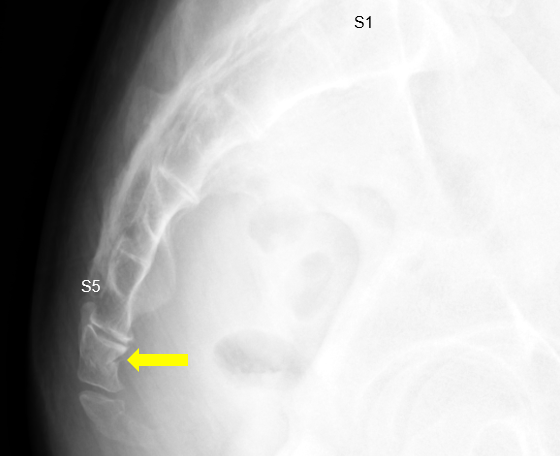

| X-ray | 골절 여부 및 관절 위치 이상 확인 |